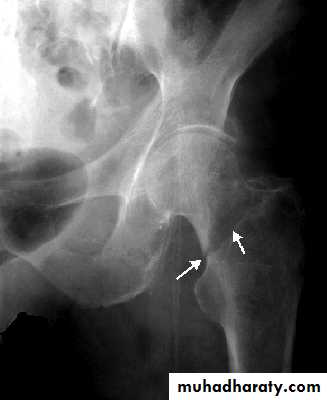

Radiological examination

two questions must be answered.Is there a fracture?

Is it displaced ?:Radiological classification

GRADE 1

:the femoral head is in its normal position or tilted into valgus and impacted on the femoral stump.GRADE 2

The femoral head is normally placed and the fracture line may be difficult to diagnosed

GRADE 3

The femoral head tilted out of position and the trabecular marking are not in line with those of innominate bone.GRADE 4

The femoral head trabeculae are normally aligned with those of innominate bone.